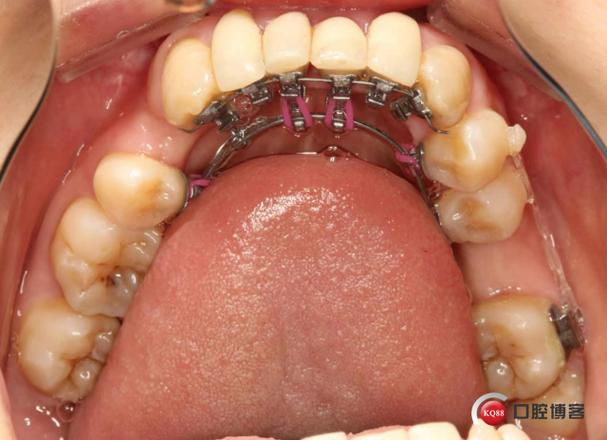

粘接与初始加力

托槽到货后,医生在口内分区域粘接(通常分上下颌两次,每次1-2小时),使用特殊粘接剂确保托槽稳固,粘接后立即放置初始弓丝,开始轻力移动牙齿,此时患者可能出现轻微酸胀、异物感,1周左右可适应。